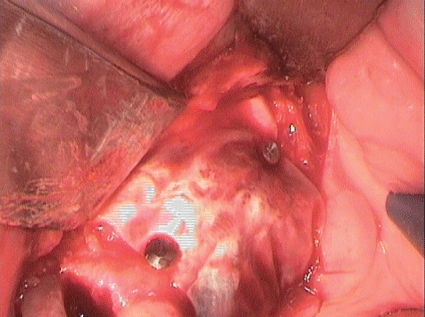

先前准备的全瓣显示手术部位在牙齿24和25周围有明显的垂直骨缺损;第24颗牙仅靠顶端附着在骨头上。根据现有的再生措施的证据,由于患者的高度顺应性,缺损被异种骨(Bio - Oss collagen, Fa。Geistlich)广泛开放刮除(光滑根表面,在超声骨刀技术的帮助下完全去除肉芽组织;(图11和12)以及pregel™和Emdogain®(Straumann GmbH)的应用。然后用可吸收的膜覆盖填充的缺陷。

图11:光滑根面24和25,用超声骨刀技术完全去除肉芽组织。

图12:光滑根面24和25,用超声骨刀技术完全去除肉芽组织。